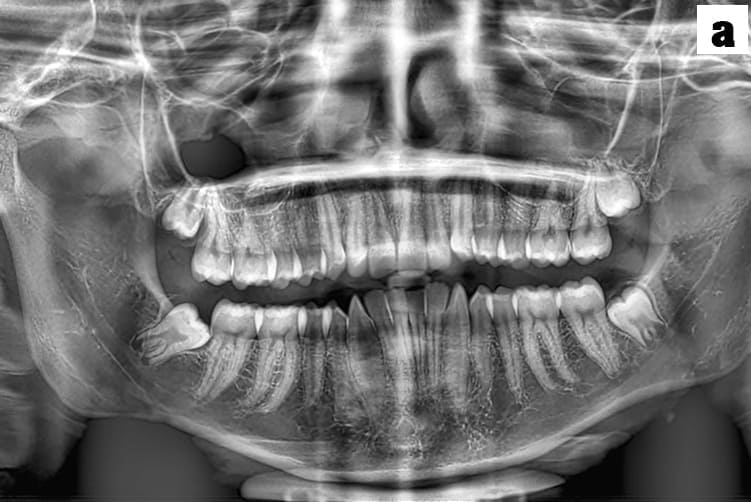

a. Migraines and TMJ disorders are diagnosed primarily through a detailed medical history and physical examination

b. For migraines, criteria from the International Classification of Headache Disorders are used, while TMJ disorders involve assessing jaw movement, tenderness and potential imaging like X-rays, MRIs or OPG to evaluate joint structure.